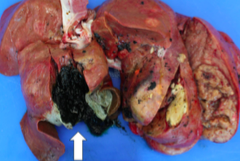

pyometra liquefactive necrosis (suppurative) purulent exudate

Front

disease type of necrosis type of exudate

Back